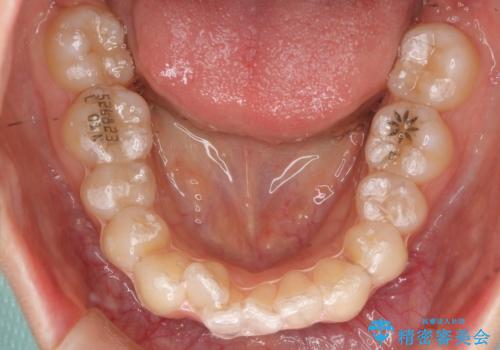

- インビザライン

- 1年7ヶ月

初回:上顎16ステージ 下顎22ステージ

リファインメント: 上顎23ステージ 下顎20ステージ

下の前歯のがたがたがそれなりにあったため、リファインメントを行いました。